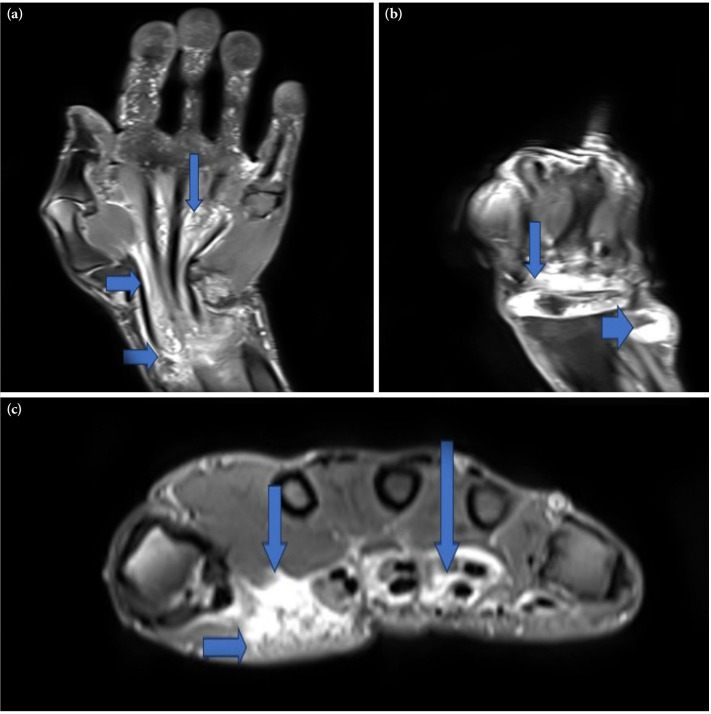

Tuberculosis is an infectious disease caused by the bacterium Mycobacterium tuberculosis. While it is commonly associated with lung involvement, it can affect other parts of the body. Approximately 10% of extrapulmonary tuberculosis cases involve bone and joint manifestations. Apart from the spine, the most commonly affected joints are the knee, hip, and ankle joints. Joint involvement can present as a slowly progressive and chronic monoarthritis. In this study, we presented a 63-year-old male patient who was diagnosed with primary tuberculosis tenosynovitis, a rare condition that can be easily confused with many clinical conditions, despite the absence of any infectious focus. In conclusion, Mycobacterium tuberculosis can involve joints, acting as an exceptional mimicker. Therefore, this pathogen should always be considered in the differential diagnosis and management of patients with arthritis.